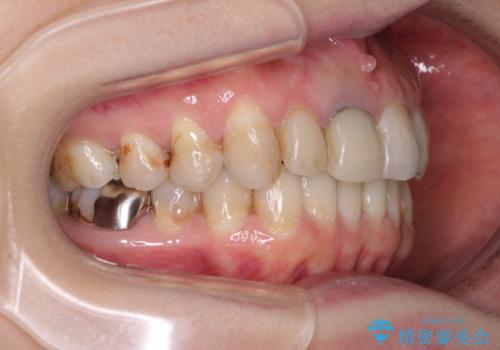

- 前歯の歯並びやむし歯治療の跡、奥歯の銀歯を気にして来院された患者様です。

インビザラインによる矯正治療の後に虫歯や銀歯をセラミックにて補綴することとしました。

前歯のむし歯治療の跡や奥歯の目立つ銀歯がなくなり、明るい口元になりました。